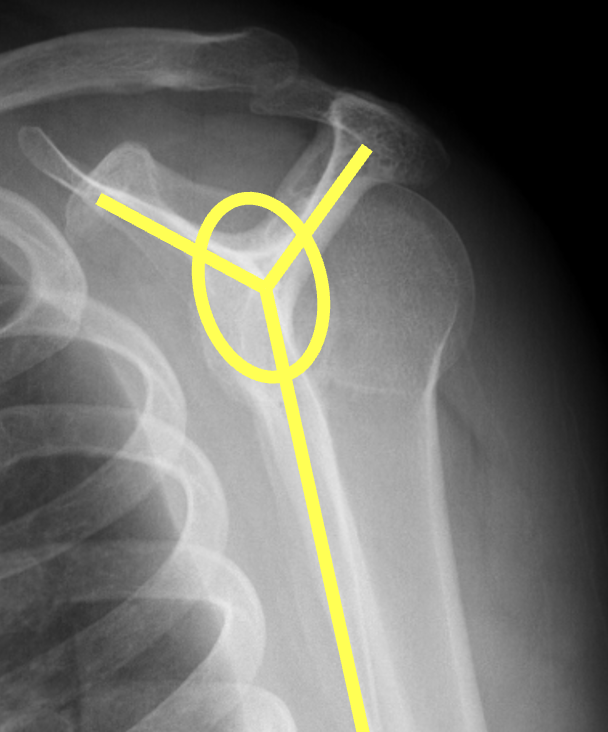

Scapular lateral

Center of the humeral head must be centered on the Y / Mercedes sign

Y is formed by

- coracoid anteriorly

- scapular spine posteriorly

- scapula body inferiorly

Normal scapular lateral

Posterior shoulder dislocation